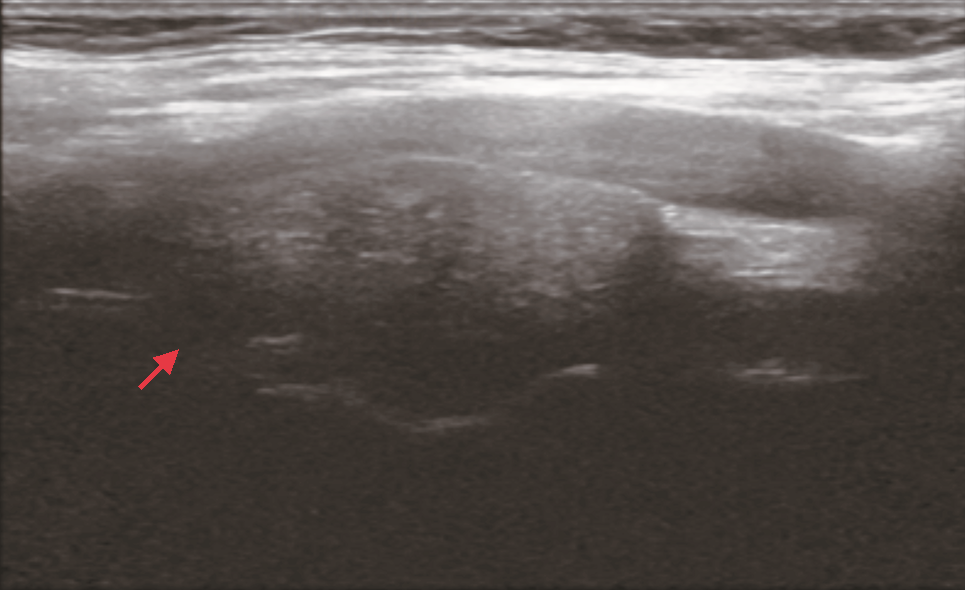

入院时查体:颈软,颈部可见5 cm横行瘢痕。右侧上颈部可及一肿物,约4 cm×3 cm,质地韧,表面光滑,可横向活动,纵向活动差未闻及杂音,未触及震颤。既往史:患者7年前因甲状腺肿物曾在外院行手术治疗,病理为结节性甲状腺肿,术后定期复查;患者高血压病史5年,自诉血压控制尚可。患者否认冠心病、糖尿病、心房黏液瘤和库欣综合征等病史。家族史:哥哥为甲状腺肿瘤患者。增强CT:右侧颈动脉鞘间隙可见一实性肿物(图1),形态欠规则,边界尚清,大小约3.5 cm×2.6 cm,增强扫描明显不均匀强化,颈内外动脉分离;提示右颈鞘肿物,倾向颈动脉体瘤。超声:甲状腺右残叶中部内侧见一个低回声结节,大小0.8 cm×0.7 cm,边界不清,左侧残叶上极内侧见一低回声结节,大小0.6 cm×0.3 cm,边界尚清;右侧中上颈颈鞘深面见一个实性肿物,大小约3.5 cm×3.5 cm(图2),向前推压至颈鞘,致颈内、外动脉夹角增大,形态欠规则,边界尚清。提示:甲状腺右叶残叶实性结节,炎性与癌待鉴别;甲状腺左叶残叶结节,良性;右颈中上颈实性肿物,良性,符合神经源肿瘤。心电图、胸部CT扫描及实验室检查未见明确异常。

患者发现颈部肿物半年并伴有典型霍纳综合征表现,体格检查肿物可横向活动,纵向活动差,未闻及杂音,未触及震颤。CT提示颈内外动脉分离,倾向颈动脉体瘤,但超声提示向前推压肿物至颈鞘,致颈内、外动脉夹角增大。综合患者病史及影像学表现,临床倾向于右上颈神经鞘瘤,来自交感神经。术前诊断:颈部神经鞘瘤,甲状腺结节(外院术后复发,不除外恶性),颈交感神经麻痹(霍纳综合征)。

MS肿瘤内含有大量黑色素颗粒,黑色素中的稳定自由基团在磁场中呈顺磁性,减少核磁中T1、T2的弛豫时间,表现出T1WI高信号,T2WI极低信号[10]。因此核磁(MRI)常常作为诊断MS的首选影像学检查,尤其是对于椎管内的MS。相比之下,CT对于椎管外MS可起到一定的诊断作用。遗憾的是,本例患者术前行CT和超声检查,综合诊断为神经鞘瘤,未行磁共振检查。我们认为,对于椎管外MS,术前高水平超声及多元化检查为MS的术前诊断可提供一定帮助,尤其是磁共振检查对术前诊断可起到极为重要的作用。